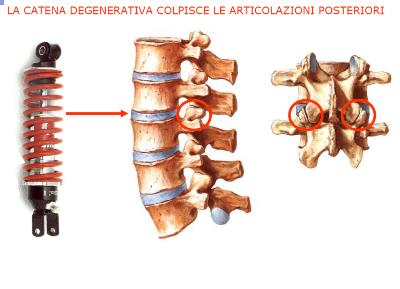

Le faccette articolari o articolazioni posteriori della colonna vertebrale, evidenziate da un cerchietto rosso nella immagine sottostante – Fig. 1, conferiscono stabilità a tutta la colonna vertebrale, sono delle piccole articolazioni che si trovano lateralmente alle vertebre e hanno il compito di stabilizzare la colonna vertebrale e limitare i movimenti eccessivi e lo scivolamento di una vertebra sull’altra.

Ogni vertebra è collegata a quella soprastante e alla sottostante attraverso le “faccette articolari” Fig.1, delimitate con un cerchio rosso.

Il danno può essere dovuto al graduale e quotidiano logoramento ma anche a traumatismi della schiena e del collo, e avviene dopo la degenerazione di un disco intervertebrale. La cartilagine che tappezza le faccette articolari viene progressivamente distrutta.

Le articolazioni diventano dolenti e rigide. Le ossa delle due vertebre si sfregano e questo può portare alla formazione di escrescenze di osso sul bordo delle articolazioni (chiamate “osteofiti”).